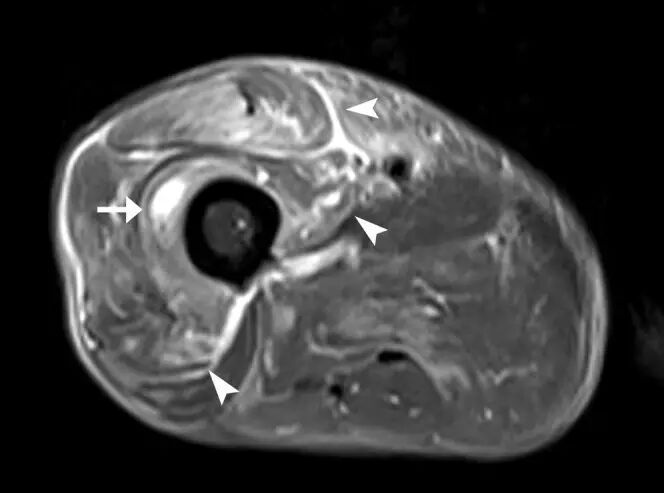

图25.一个67岁的男性结节型肌肉结节病,左大腿软组织包块,伴随腿疼痛。 (a)轴向T1加权磁共振图像显示在左腿的腓肠肌和胫骨前肌中的低信号强度结节(箭头)。 (b)轴向T2加权的MR图像显示由高信号强度(箭头)的厚边缘包围的中心低信号强度的肌内小腿损伤(箭头)。 ,在四头肌(箭头)中具有急剧的边缘状增强。 活检揭示非梗阻性肉芽肿。 T,胫骨。

![]()